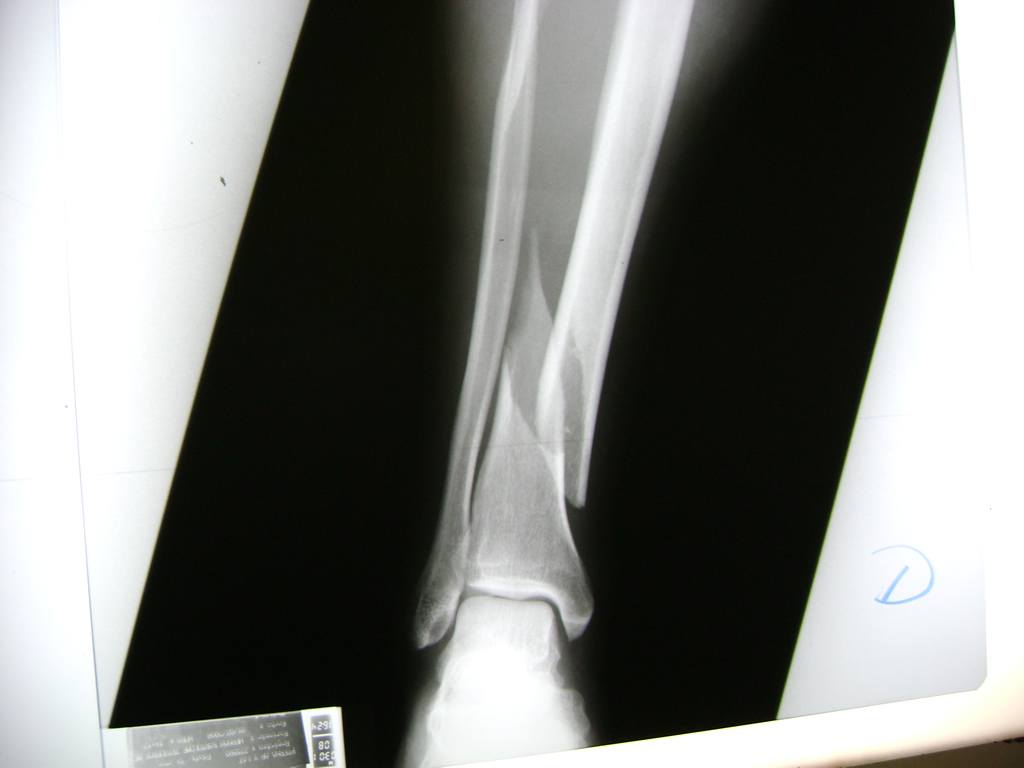

Calcaneo - Perone y Tibia

Aunque cada uno de estos huesos puede fracturarse por separado, normalmente la rotura es una lesión que se produce de forma conjunta

La mayor parte de las roturas implican a la parte proximal del hueso (parte del hueso próximo a la rodilla) o a la parte distal (parte del hueso cerca del tobillo).

Debido a la fina cobertura de piel que recubre la tibia y el peroné, las fracturas generalmente son abiertas, es decir, el hueso roto rasga la piel, atravesándola. Las fracturas de tibia y peroné generalmente se producen por un fuerte impacto o torsión.